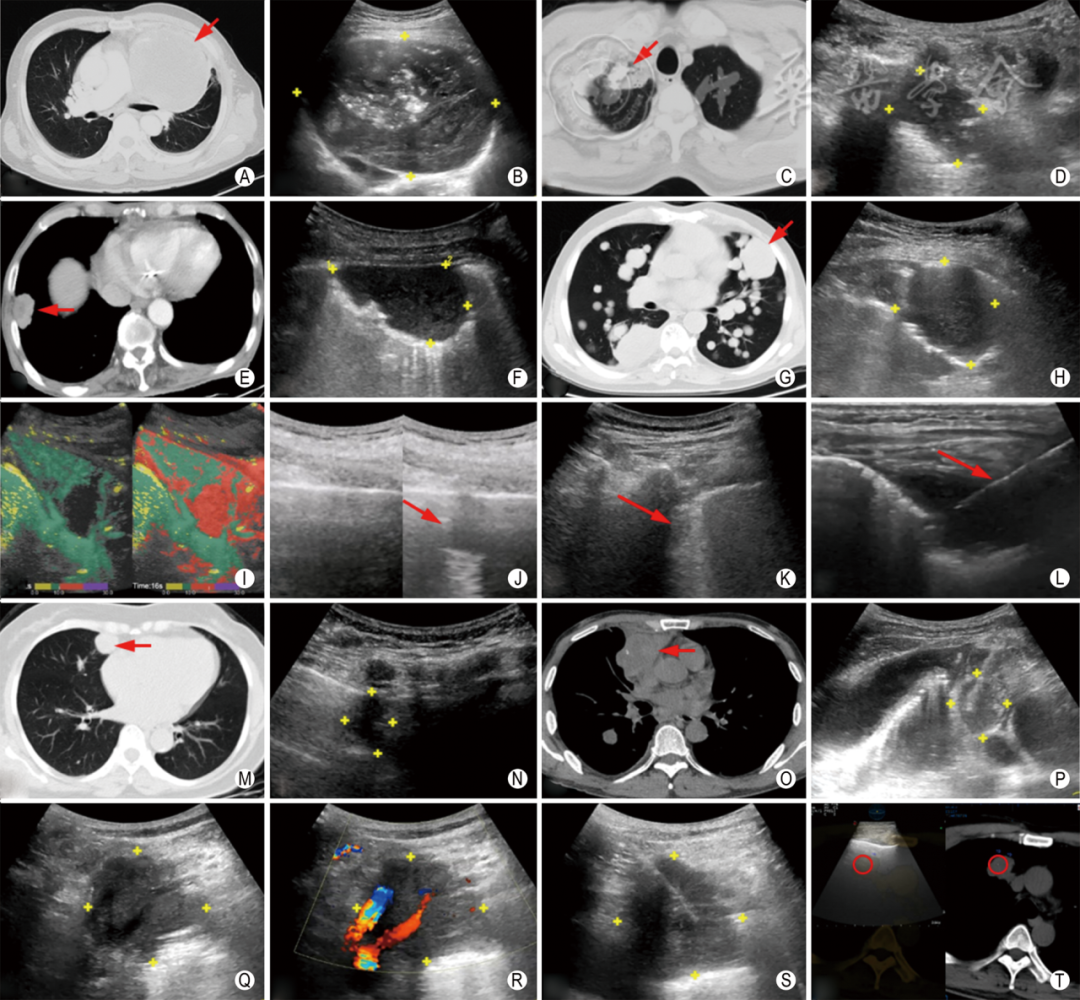

(二)胸膜下肺病灶以周围型为主(图1 A~H)。部分中央型病灶伴发的肺不张、肺实变或胸腔积液形成病灶与胸壁间的“声窗”,均可为超声成像和引导经皮穿刺活检提供条件(图1 I)。

图1  超声引导经皮肺穿刺活检的特点 左肺上叶(A、B图)、右肺尖(C、D图)、右肺下叶(E、F图)的单发结节或肿块、双肺多发结节及肿块(G、H图)适用于超声引导经皮穿刺活检(红色箭头或黄色十字标记所示为病灶)。中央型肺肿瘤伴肺实变可被超声显示,超声造影时间参量图中周围绿色部分为实变肺组织,中央红色部分为肿瘤病灶(I图)。吸气时,超声无法显示肺病灶(J图左),呼气时,病灶清晰显示(J图右,红色箭头所示)。后背部(K图)较前胸部(L图)病灶深,无法通过高频探头显示,穿刺路径更长,操作难度更高(红色箭头所示为穿刺针)。心脏(M、N图)、大血管(O、P图)、颈部大血管(Q~S图)旁病灶超声引导经皮穿刺活检安全性高(红色箭头或黄色十字所示为病灶)。超声与CT图像融合后可引导非胸膜下肺病灶经皮穿刺活检(T图,红色圆圈所示为病灶)

(四)肺脏具有自主呼吸运动,下肺呼吸动度明显大于上肺,对于不能呼吸配合的患者,下肺病灶穿刺难度大于上肺病灶(图1 J)。

(五)背部肌肉较前胸厚,病灶位置更深,穿刺难度更高(图1 K,L)。

(六)随呼吸移动明显、位于心脏或大血管旁、位于肺尖且紧邻颈部大血管等高风险部位的小病灶,通过超声引导穿刺活检可提高成功率、降低并发症发生率(图1 M~S)。

(七)超声显示不清晰,或病灶与胸壁间有少许含气肺组织,导致肺病灶无法显示的,可在影像融合容积导航技术引导下穿刺活检,借助CT容积图像引导超声定位病灶,拓宽超声的适用范围(图1 T)。